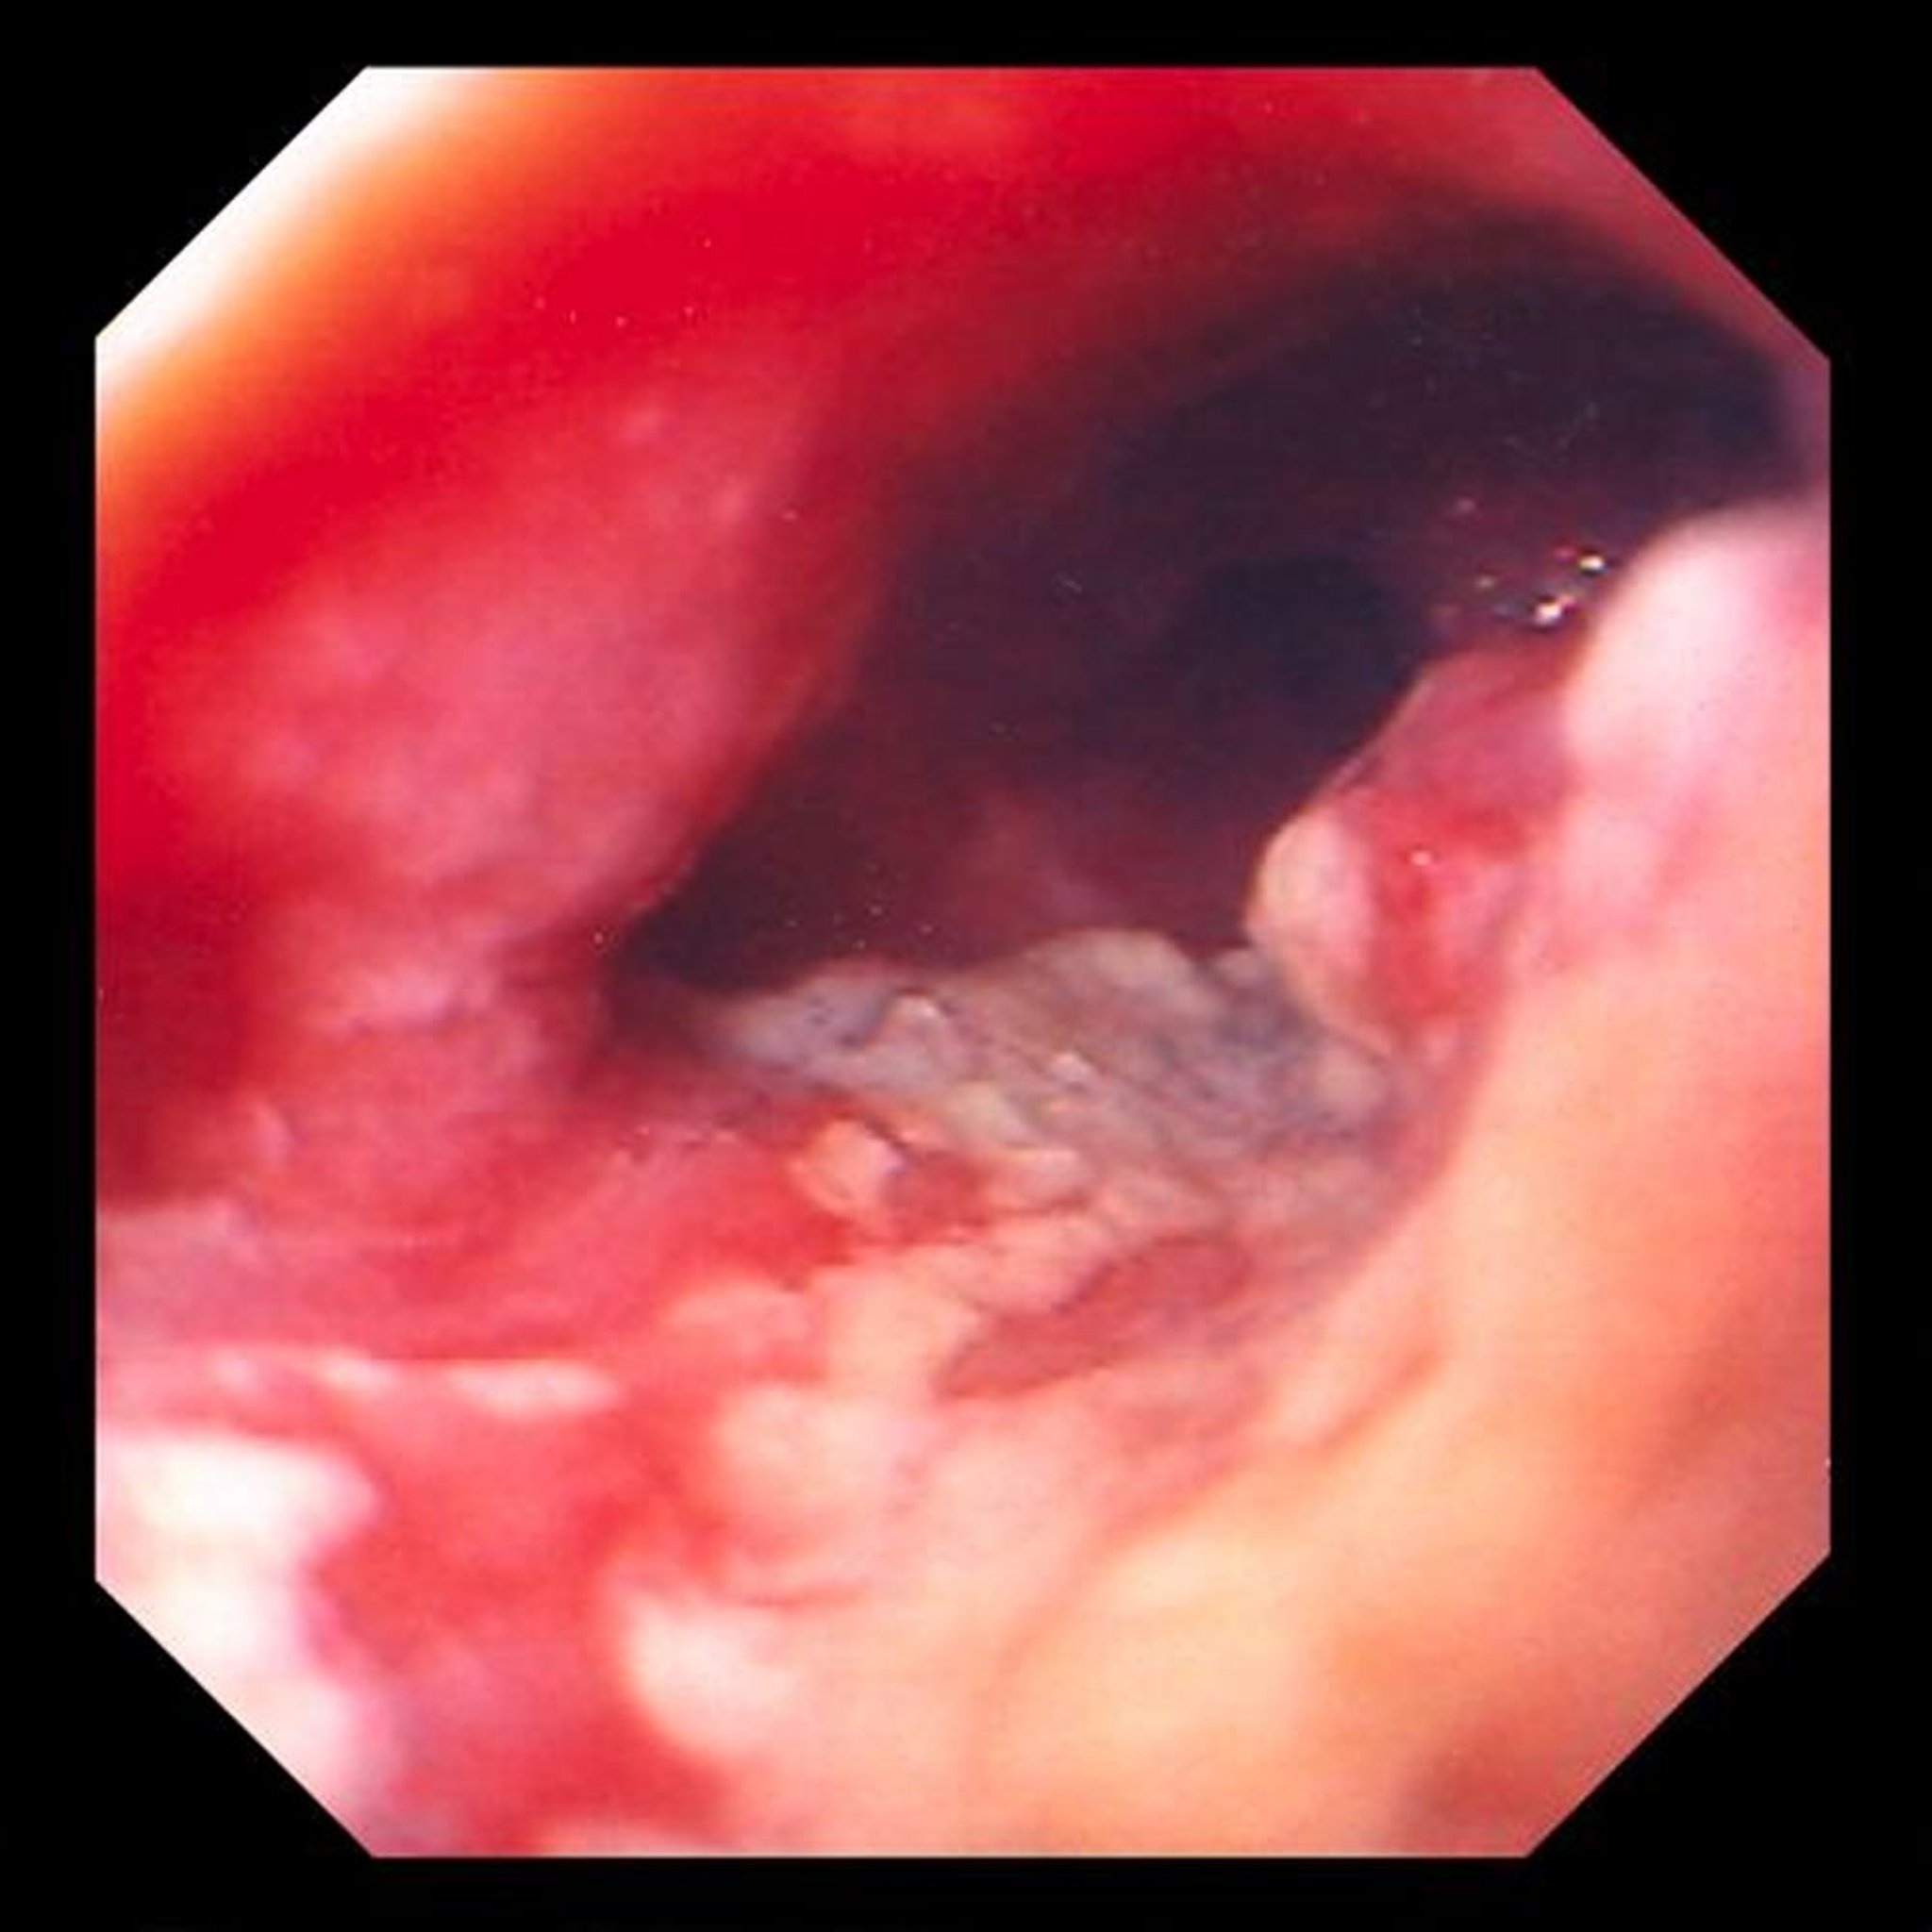

Аденокарцинома пищевода

Это изображение показывает язвенную сдавливающую опухоль, расположенную в дистальном отделе пищевода, что наводит на мысль об аденокарциноме, возникающей в результате метапластических призматических изменений (пищевода Барретта).

Image provided by David M. Martin, MD.